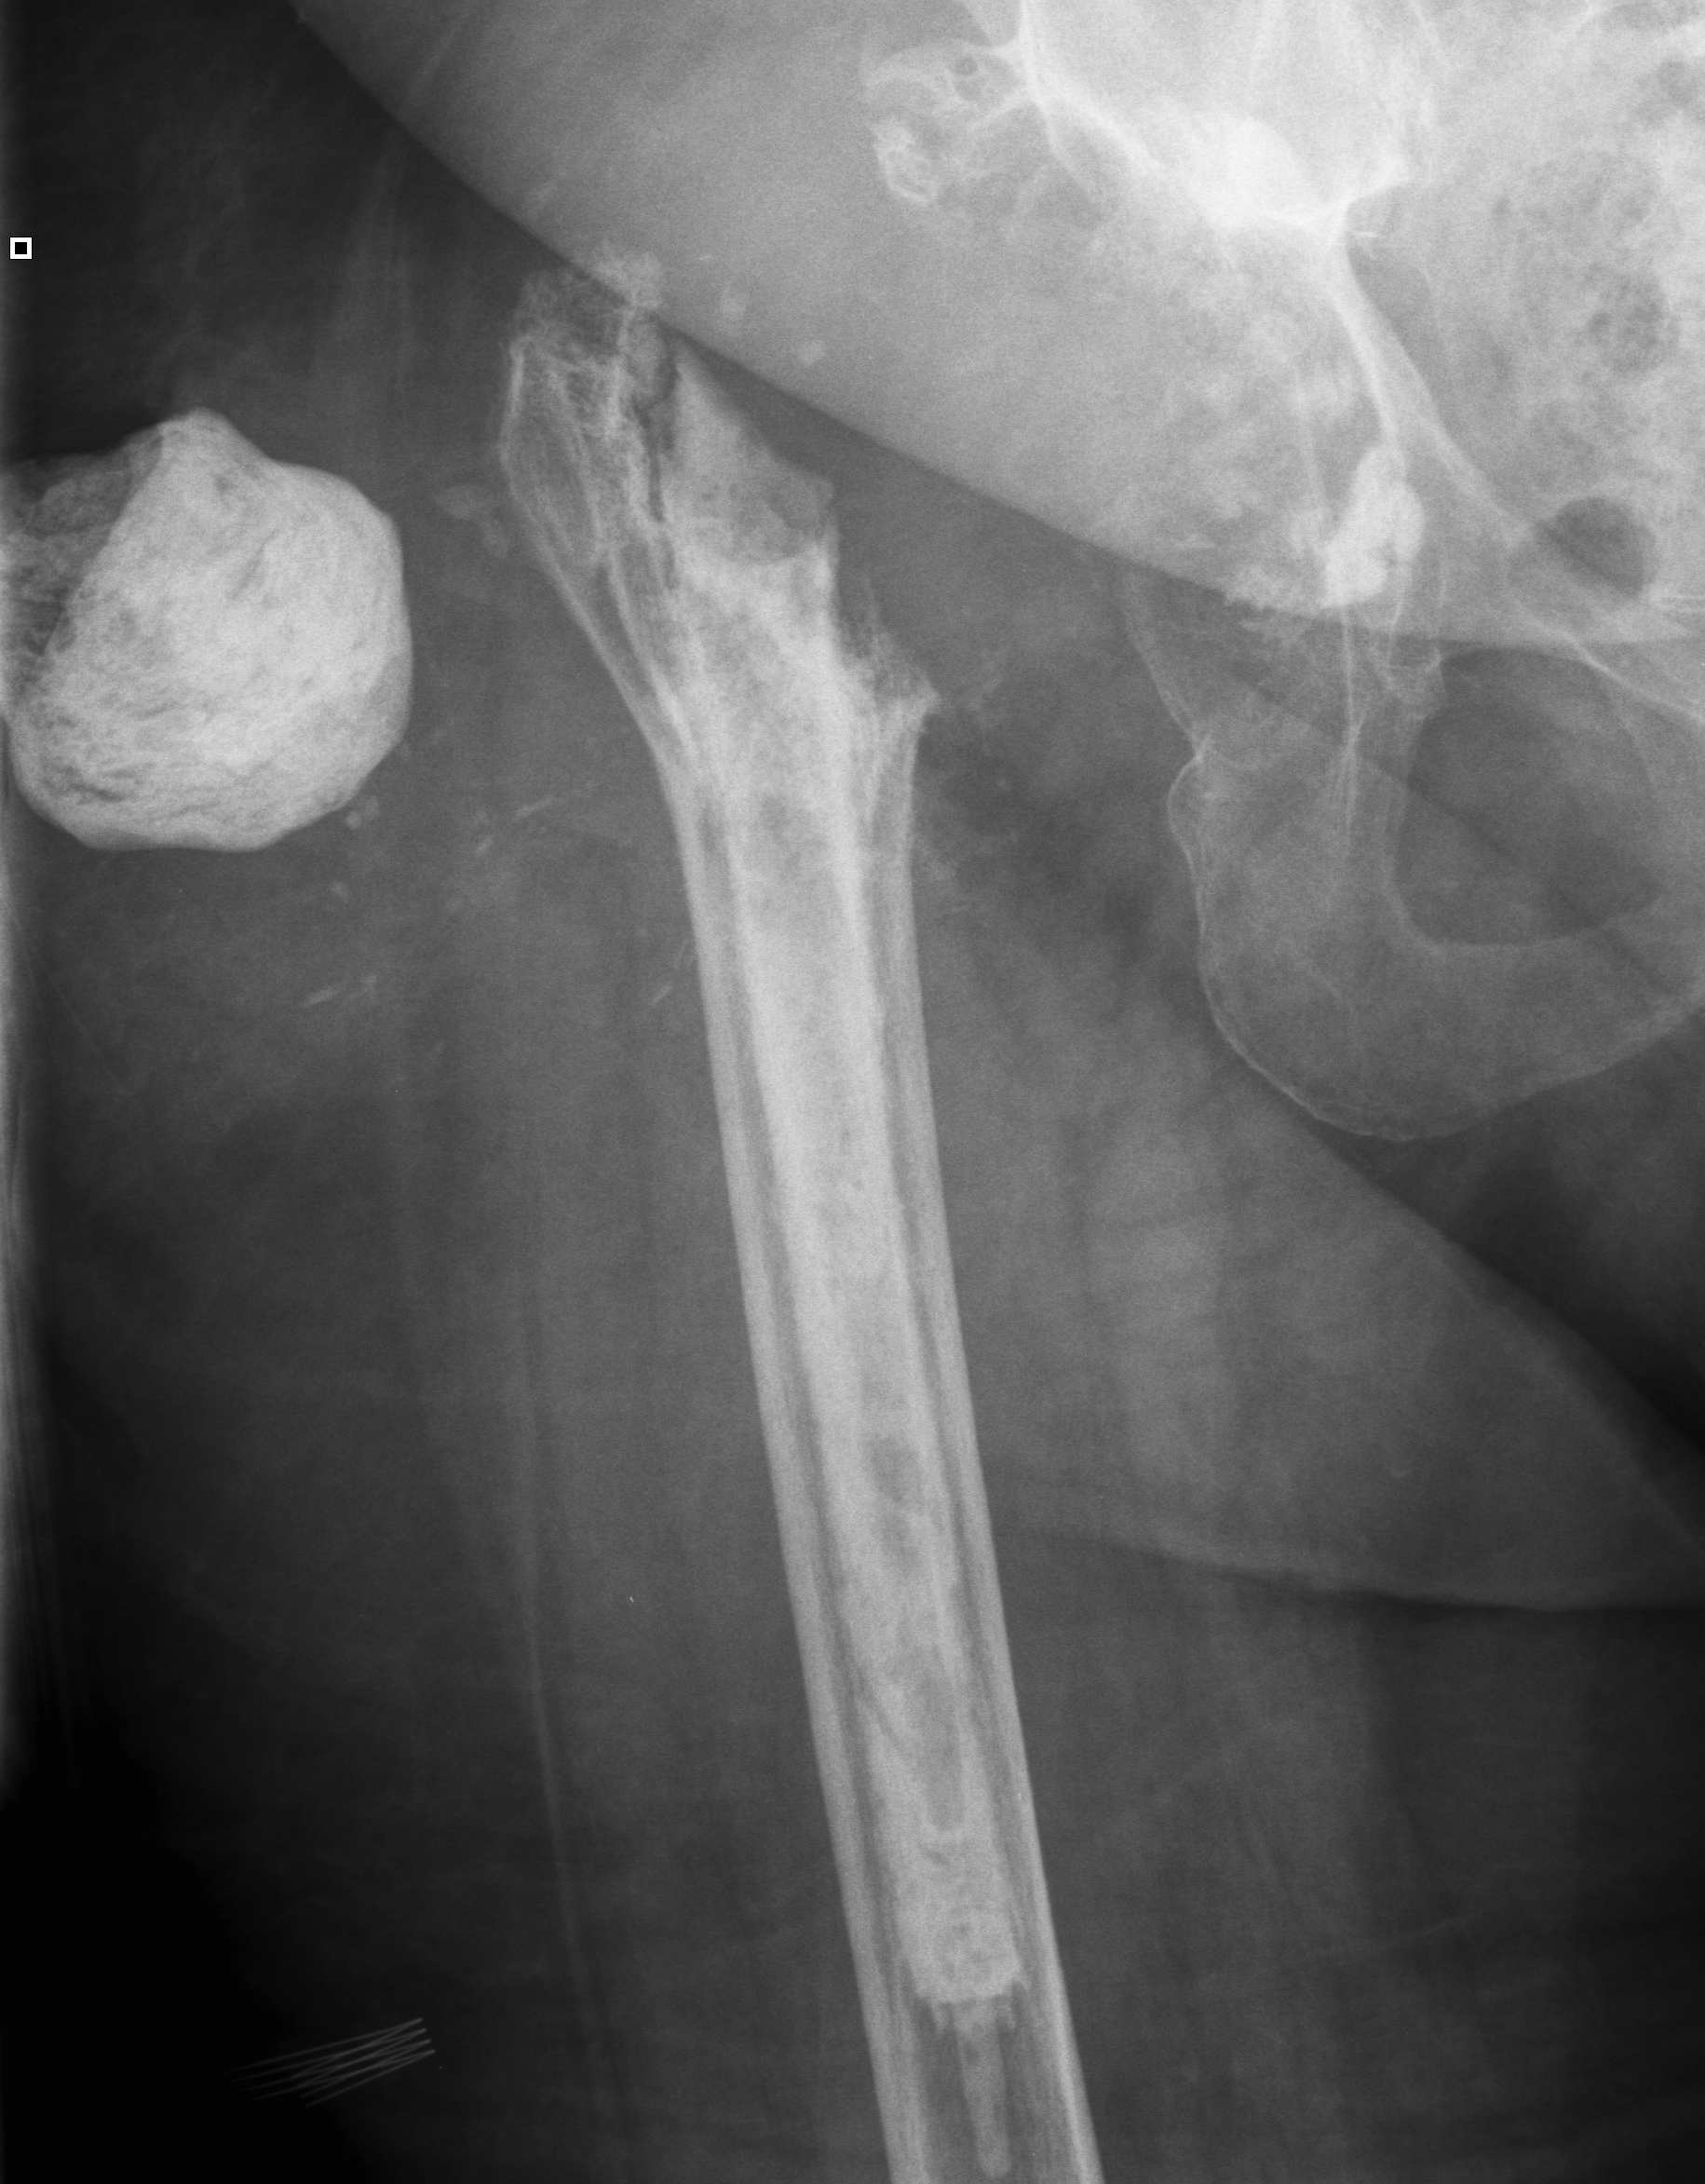

Resection Arthroplasty / Girdlestone

Indications

- medically unfit for further revision surgery

- refusal for further revision surgery

- sepsis control / virulent bug

- unrevisable due to bone loss

- unlikely to become mobile